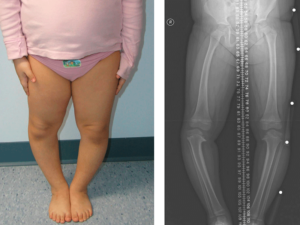

پای پرانتزی در کودکان؛ علائم و بهترین روش درمان

پای پرانتزی در کودکان یکی از اختلالات شایع در دوران رشد است که در آن زانوها به صورت غیرطبیعی از هم فاصله میگیرند و پاها به شکل پرانتز دیده میشوند.